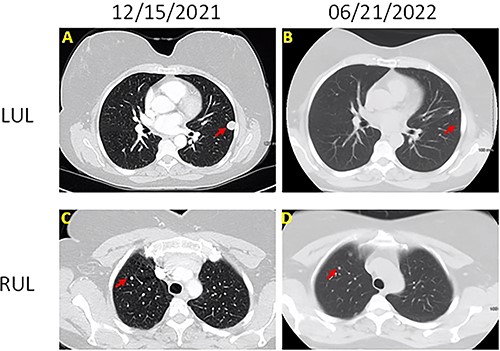

The patient was a 60-year-old female who presented with persistent shortness of breath for 1 year. Chest computed tomography (CT; Fig. 1) with contrast showed a 1.5-cm well-circumscribed, homogenous, noncalcified nodule in the left upper lobe and multiple similar, but smaller (3–5 mm), nodules involving right upper, right lower and left lower lobes. Positron emission tomography (PET)-CT revealed that the 1.5-cm nodule was hypermetabolic with SUV of 5.2 and suspicious for malignancy. The other smaller nodules were not detected by PET scan.

Chest CT images of the lesions (A) left upper lobe lesion (1.5 cm) before surgery on 15 December 2021; (B) left upper lobe lesion after surgery on 21 June 2022; (C) right upper lobe lesion (0.5 cm) on 15 December 2021; (B) right upper lobe lesion on 21 June 2022; there is no change on the size.

Left upper lobe wedge resection was performed. On gross examination, the nodule was tan-white, well-circumscribed, firm, homogeneous, measuring 1.5 × 1.3 × 0.7 cm, abutting the pleura. Microscopically, this tumor was composed of bland epithelioid and spindle cells with moderate amount of cytoplasm, whorl formation and occasional pseudo-nuclear inclusions (Fig. 2). No mitoses or necrosis was identified. Tumor cells were positive for epithelial membrane antigen (EMA), progesterone receptor (PR), somatostatin receptor 2a (SSTR2A) (Fig. 2) and S100. CNS meningioma was ruled out clinically. The overall findings support the diagnosis of PPM. The patient was doing well on a 3-month follow-up after wedge resection. All the small nodules remained unchanged on chest CT.

Of note, PPM in our case also presents with associated multiple micronodules, ranging in size from 3 to 5 mm. This manifestation is rare, and very few similar cases have been reported [7–9, 33]. In two of these cases, different nodules were sampled, and histology confirmed the diagnosis of multiple PPM [7, 8]. For other cases, the diagnosis was based on the histology of the largest lesion, and small nodules were on active surveillance [9, 33]. This multiple-nodule presentation can easily be confused with lung metastasis or advanced lung cancer [9].